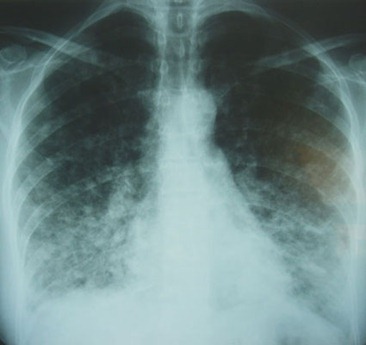

- Radiografía de Tórax